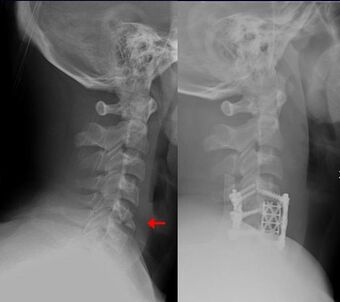

| Teardrop fracture of the cervical spine before and after treatment with metal fixation |